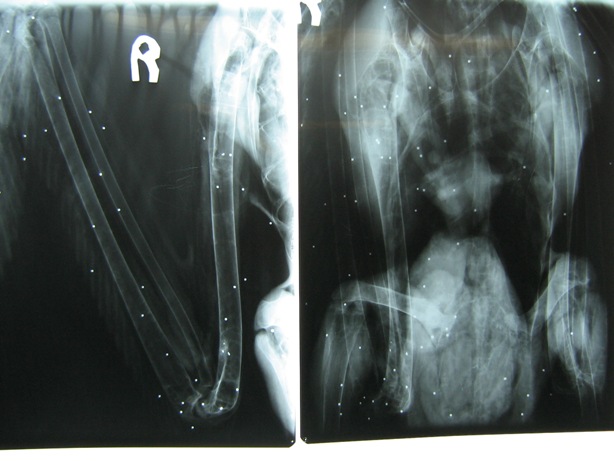

עונת הנדידה של השקנאים בעיצומה, ובמהלכה עתידים לעבור בארץ יותר מ- 70 אלף שקנאים בדרכם מאירופה לאפריקה. כ-40 אלף מהם נוהגים לעבור דרך עמק החולה והיתר נודדים לאורך חוף הים התיכון. חובבי הטבע והצפרים מקבלים אותם בברכה, אולם דייגים רבים לא ממש מתלהבים. זאת משום שהשקנאים מסבים נזק לענף הדיג, מכיוון שהם נוהגים לשלות "צידה לדרך" מתוך בריכות הדגים. כמה דייגים החליטו לפתור את הבעיה בדרך קשה ואכזרית – הם פשוט יורים בשקנאים, במטרה לגרש אותם מהאזור. כך, למשל, נמצאו מעל 100 כדוריות עופרת בגופו של שקנאי שנמצא בשבוע שעבר בנמל חיפה והובא לטיפול רפואי על ידי אנשי רשות | | בגופו של השקנאי הירוי נמצאו מעל 100 כדוריות עופרת | צילום: אוהד הצופה, רשות הטבע והגנים |

הטבע והגנים. השקנאי זוהה על ידי דייגים אחרים, שדיווחו על כך לד"ר עוז גופמן מהמכון לחקר יונקים ימיים ולפקח רשות הטבע והגנים, שי קורן, שהצטרפו לפעולת ההצלה בעזרת שוטרי צוות השיטור הימי. באותו יום נמצא באותו האזור שקנאי ירוי נוסף. שני השקנאים עוברים בדיקות וטיפולים ויועברו השבוע לשמורת החולה לתהליך הבראה ושיקום. האנשים שהיו מעורבים בירי על השקנאים נתפסו על ידי פקחי רשות הטבע והגנים והוגשה נגדם תלונה. באירוע אחר שהתרחש אתמול (שני) נתפסו אנשי המדגה של מעגן מיכאל כשהם יורים והורגים תשעה שקנאים ופוצעים נוספים. כנגד החשודים נפתח תיק פלילי. אוהד הצופה, אקולוג העופות של רשות הטבע והגנים אומר כי רשות הטבע והגנים הציעה פתרון המאפשר ללהקות השקנאים לאכול במרכזי האכלה בבריכות שיועדו לכך, ולהמשיך בנדידה. הדגים שיאכלסו את הבריכות הללו אינם גדולים וממילא אינם סחירים. "הדבר יאפשר לשקנאים לאכול ולהמשיך בנדידה מבלי לפגוע בפרנסתם של הדייגים. צריך להבין שהשקנאים חייבים לעצור כאן ולהצטייד במזון בדרכם מעל המדבר, מכיוון שלאחר מכן הם אינם אוכלים במשך זמן רב", אומר הצופה. פתרון דומה יושם בעמק החולה, שם סבלו החקלאים מנזקים שגרמו עגורים במהלך נדידתם. באזור הוקמו תחנות האכלה מיוחדות עבור העגורים, כדי שלא יפגעו בגידולים החקלאיים. צופה מוסיף כי הציד הלא חוקי פוגע במגוון הביולוגי בדרכים נוספות. כדוריות הציד מכילות עופרת, וזו מגיעה בסופו של דבר גם אל תחתית מימי בריכות הגידול ומרעילות דגים ועופות הניזונים ממזון בקרקעית.  | | בכל חודש מטופלות עשרות ציפורים פצועות | צילום: דידי קפלן, רשות הטבע והגנים |